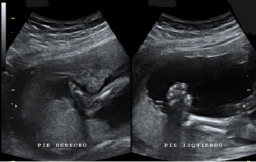

A lo largo del embarazo, el médico te recomendará una serie de pruebas diagnósticas para asegurarse que tu hijo se desarrolla correctamente, como la ecografía. Otras solo se prescriben cuando el ginecólogo sospecha que algo puede ir mal y necesita más datos para corraborarlo, como la amniocentesis o el control del bienestar fetal. Te contamos cómo y cuándo se realizan.